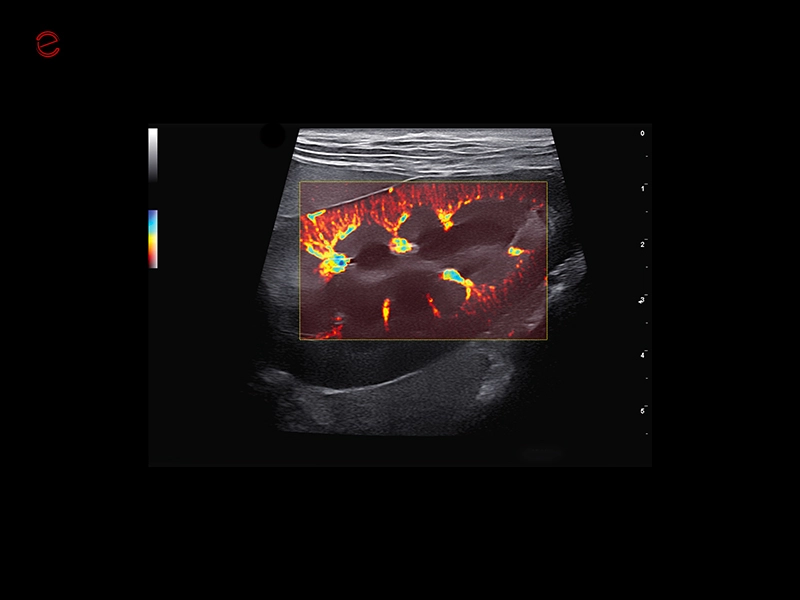

HIGH-RESOLUTION IMAGING IN ALL APPLICATIONS

Unmatched vision

Herons have exceptional eyesight, enabling them to detect subtle movements even in challenging conditions, making them highly effective hunters. Similarly, MyLab™Heron offers incredibly detailed and high-resolution imaging, in superficial areas as well as in deeper ones, thanks to the wide range of probes. All this makes it possible to scan from the smallest to the biggest animals in all applications covering general imaging, cardiology, musculoskeletal, reproduction, and ensuring unmatched clarity in all your examinations.